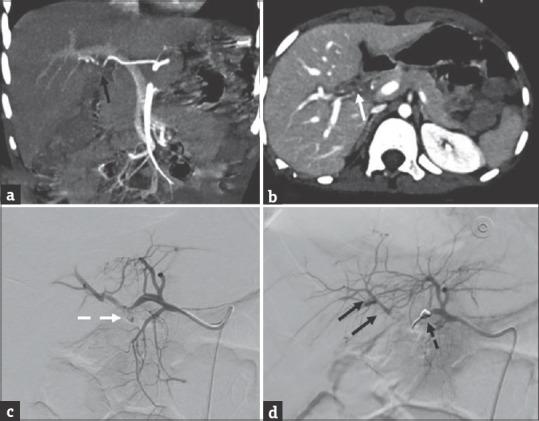

Choledochal cysts (CDC) are rare biliary tract anomalies characterized by congenital dilatation of the extrahepatic and/or intrahepatic bile ducts. CDC excision with hepatico-enterostomy is the preferred surgery in modern era. Perioperative blood loss in a case of laparoscopic choledochal cyst excision (LCCE) is usually minimal and managed by conservative treatment such as blood transfusion and correction of coagulation factors. Massive hemorrhage in LCCE is rare and reported intraoperatively or within the first 3 postoperative days. Hereby, we present an unusual case of arterio-duodenal fistula, post LCCE presenting as delayed massive upper gastrointestinal bleeding in a male child and its successful endovascular management.

胆总管囊肿(CDC)是一种罕见的胆道畸形,其特征为肝外和/或肝内胆管的先天性扩张。在现代,胆总管囊肿切除并肝肠吻合术是首选的手术方式。腹腔镜胆总管囊肿切除术(LCCE)病例的围手术期失血量通常很少,通过输血和纠正凝血因子等保守治疗进行处理。LCCE术中出现大出血的情况罕见,多在术中或术后第1个3天内报告。在此,我们报告一例LCCE术后罕见的十二指肠动脉瘘病例,该病例表现为一名男童延迟性上消化道大出血及其成功的血管内治疗。